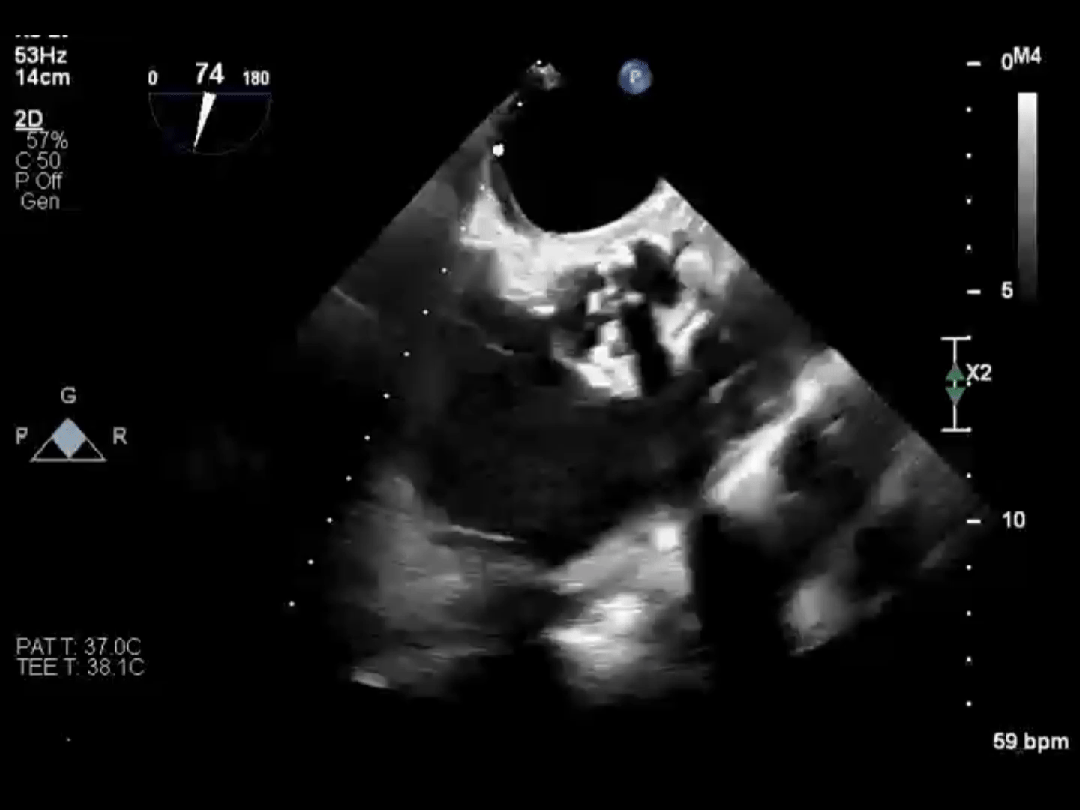

同样幸运的还有李爷爷。他因心脏二尖瓣脱垂导致血液严重反流,随时可能发生心衰。经过评估,医生为他选择了经导管二尖瓣钳夹术(TEER)。

手术中,医生通过大腿静脉送入特制夹子,在超声引导下精准夹合脱垂的瓣叶。整个手术不到 1 小时,李爷爷原本关不牢的「心门」变得「严严实实」,术后反流明显减少,充分彰显了团队的技术实力。